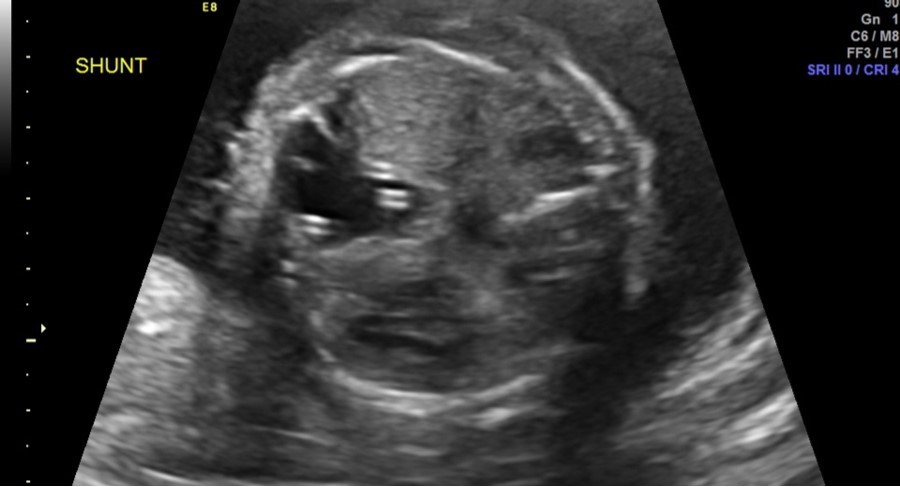

Follow-up parental microarray showed that the 16p11.2 microduplication was maternally inherited. This duplication can be linked with an increased risk of autism or other early onset psychological or neurodevelopmental abnormalities. Fetal MRI was performed at 25 weeks 5 days, noting a large left hemithorax multicystic lesion consistent with CPAM as well as right lung hypoplasia, fetal hydrops, and polyhydramnios. Serial ultrasounds following shunt placement (Figure 2) and CVR (Table 3) noted dislodged shunts on three occasions. With the dislodged shunts, the dominant cyst significantly increased, as did the CVR. On these three occasions (at 24 weeks 3 days, 28 weeks 3 days, and 31 weeks 3 days) repeat thoraco-amniotic shunts, two per procedure, were placed. Immediately after each shunt placement the CVR was notably decreased (Table 3). Amniodrainage was performed at shunt placement when necessary.

Figure 2.Two thoraco-amniotic shunts can be seen in the dominant CPAM cyst